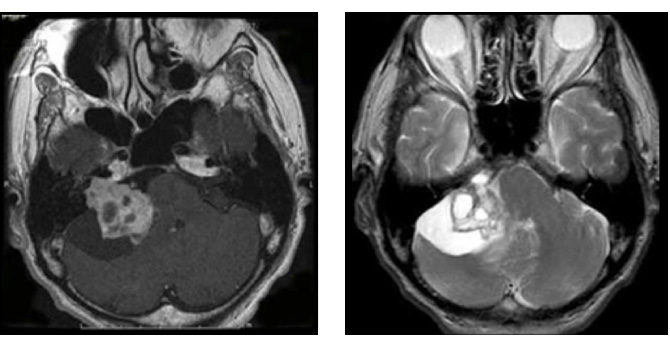

図1:20代男性 聴神経腫瘍

(左図)術前MRI:術前聴力は10dB

(右図)術後MRI:内耳道に筋肉片がおかれている術後聴力は温存16dB 顔面麻痺はなし

図1は若い男性で大きめの腫瘍であったため手術にて摘出しました。術前聴力は良好で、術後もほぼ聴力は変化なく、また顔面神経麻痺も出現していません。